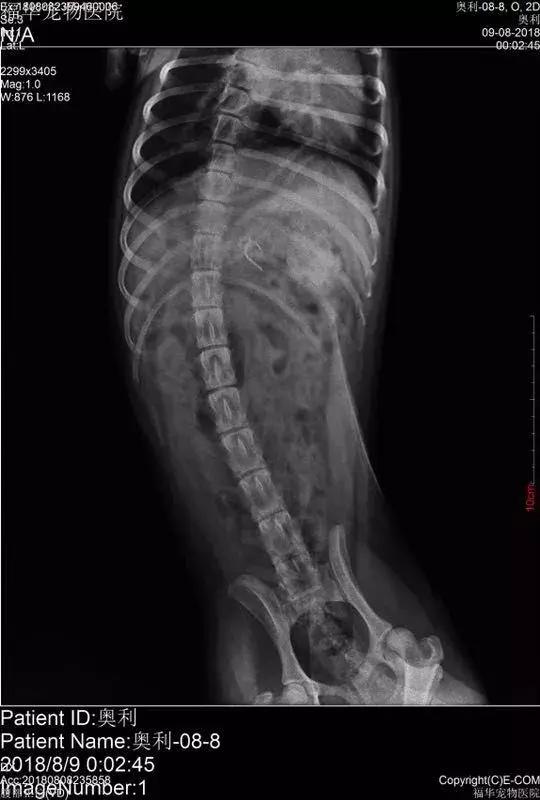

“该不会狗狗也吃了这些火腿肠吧?” 陈太太一想到这里,马上联系了女儿,连夜将小狗送到了宠物医院治疗。在给狗狗拍了片之后,医生果然发现一个鱼钩已经溜到了它的身体里。

经过医生连夜抢救和治疗,这个险些要命的鱼钩终于被取了出来。